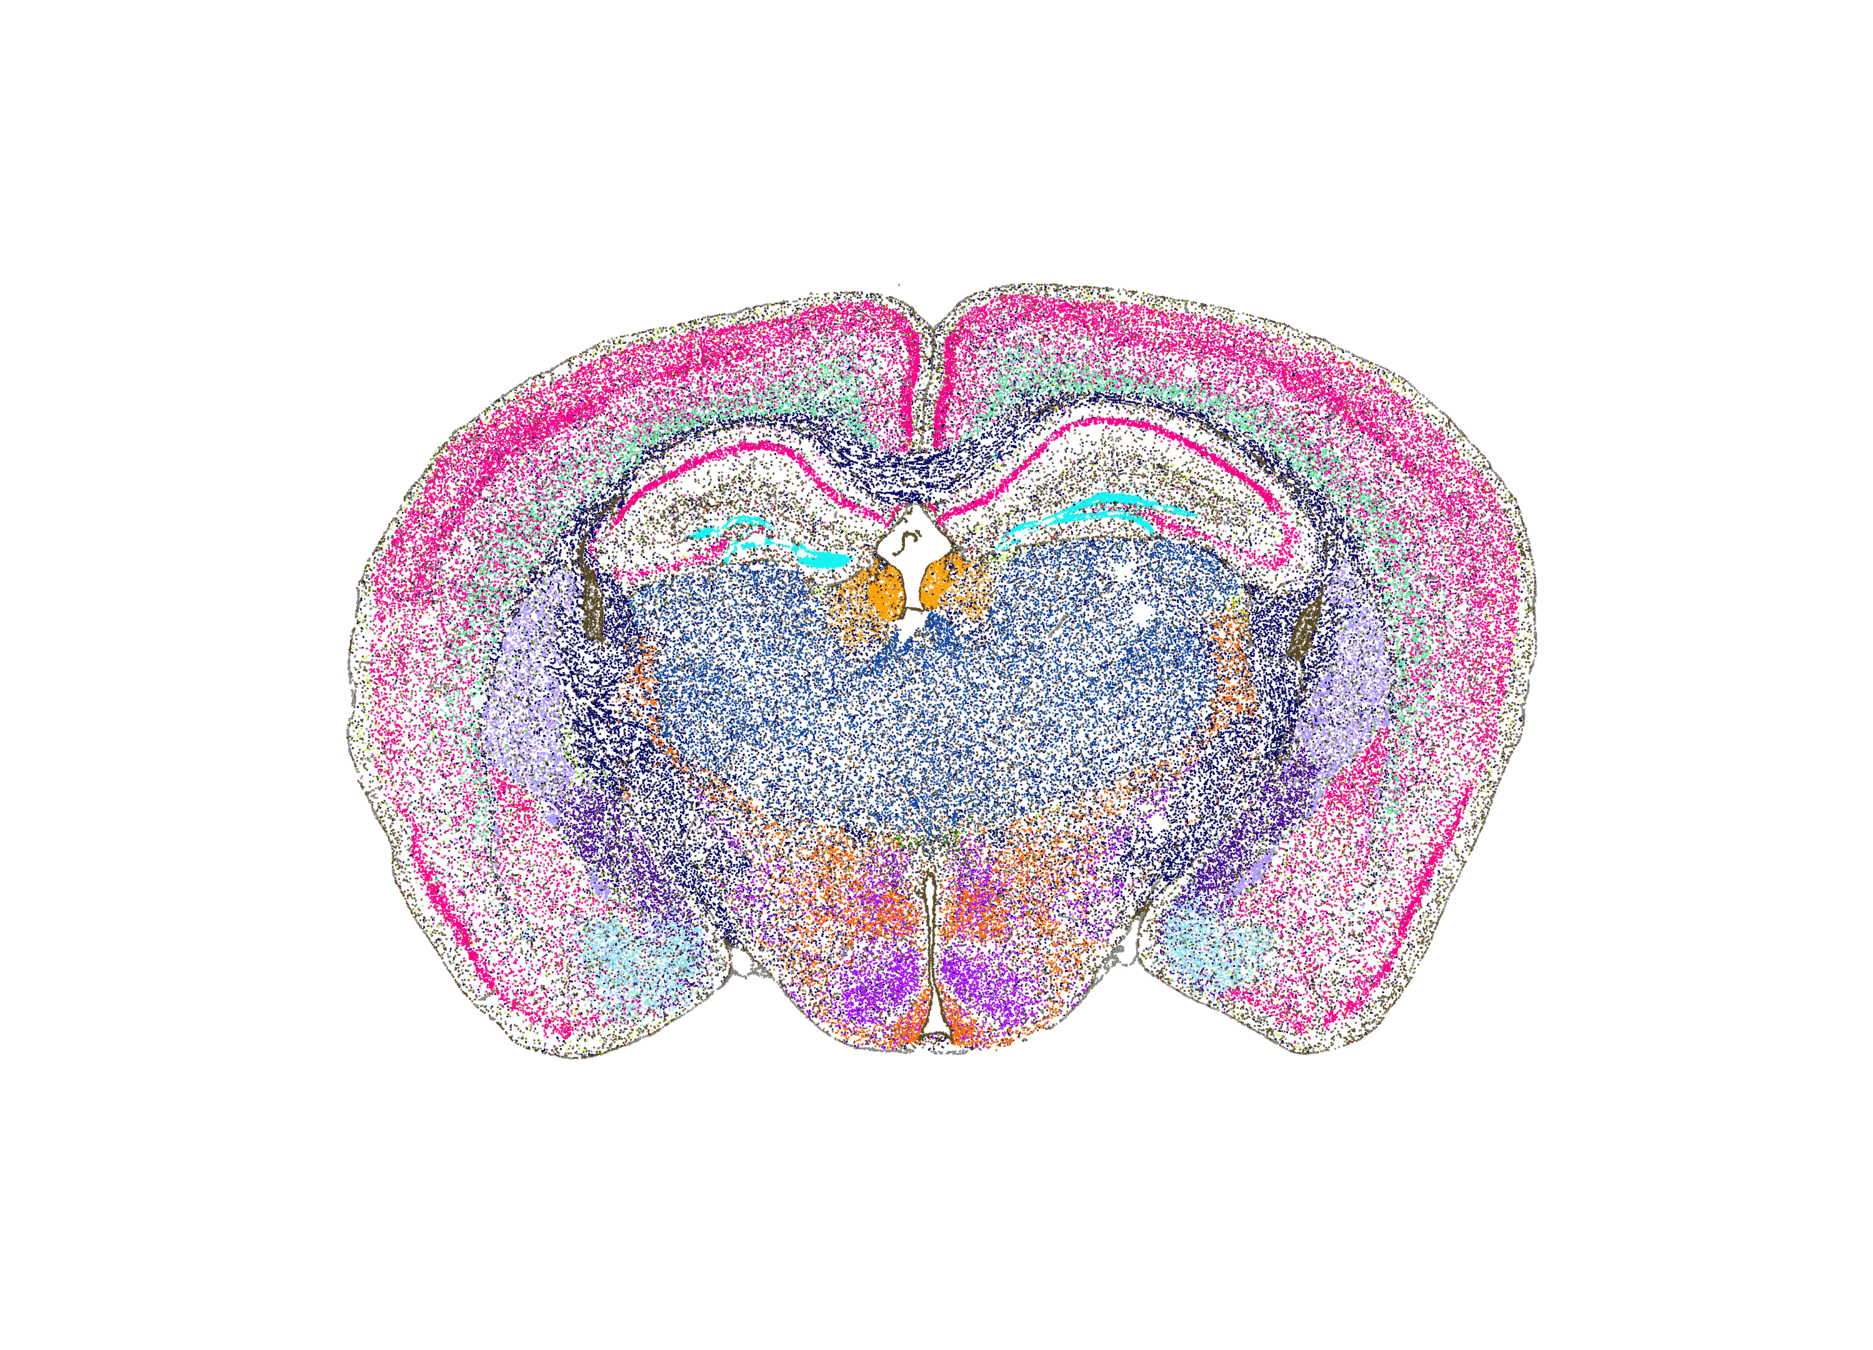

Spatial transcriptomics

Breast Cancer: data

• 37 proteins simultaneously (independent channels)

• n = 693

• 32 cell phenotypes are identified from different protein expressions

- e.g. a cell expressing \(\texttt{CD3}\) and \(\texttt{CD8}\) is (likely) a \(\texttt{cytotoxic T cell}\)

a cell expressing \(\texttt{CD68}\) is likely a \(\texttt{macrophage}\)

[Danenberg​ et al, 2022]

• Imaging Mass Cytometry (IMC): "large" and new datasets of protein expression